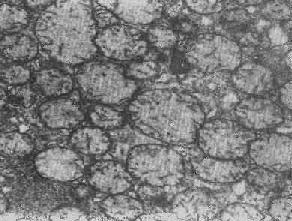

心肌细胞线粒体

图1-8 心肌细胞线粒体